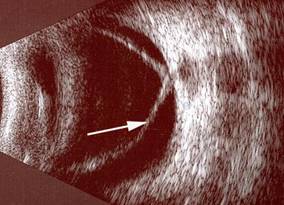

Resim 3: Normal göz ultrasonografi görüntüsü. Gözün arkasını dolduran göz sıvısı (vitreus) beyaz okla, retina tabakası siyah okla gösterilmektedir.

Resim 4: Yandaki resimde retina dekolmanı olan hastanın ultrasonografisi izlenmektedir. Retinanın normal yerinden ayrılıp öne doğru geldiğini görmek mümkündür (beyaz ok).